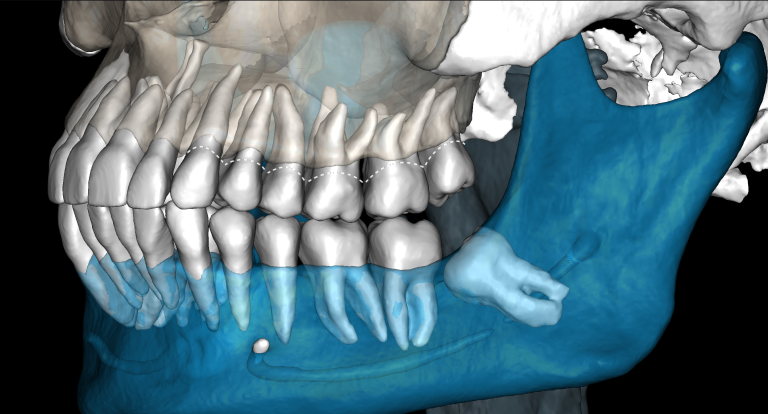

«Эндодонтический отчет» Diagnocat помогает зафиксировать изначальный объем периапикального очага и изучить анатомию и морфологию корневых каналов до начала лечения